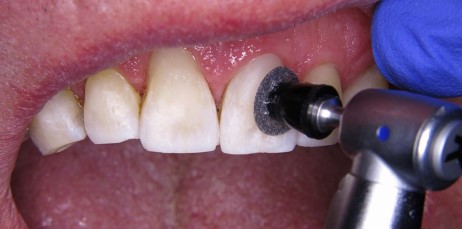

Po zastosowaniu miejscowego środka znieczulającego oczyszczono powierzchnię leczonych zębów pastą profilaktyczną bez fluoru Cleanic (KERR GmbH, Biberach). Stosując podejście minimalnie inwazyjne i względną izolację usunięto wiertłami z nasypem diamentowym i różyczkowym istniejące wypełnienia oraz tkanki zmienione próchnicowo (ryc. 3). Kolor zębów oceniano w oparciu o wilgotne zęby przed założeniem koferdamu.

Ryc. 3. Obraz po minimalnie inwazyjnym usunięciu próchnicy i opracowaniu ubytków.